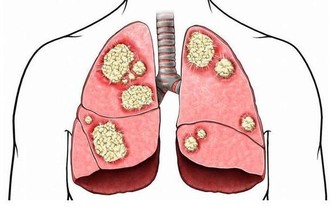

可是,你要當心了,不斷出現腹脹可能是卵巢癌的體徵和症狀之一。

和其他幾乎所有癌症一樣,卵巢癌難以識別,特別是在早期階段。但它終究不是毫無跡象可尋。

而腹脹,就是其中一個警示信號。如果大家了解卵巢癌的各種早期症狀,

比如持續性腹脹,並能儘早把這些症狀與卵巢癌聯繫起來,就會挽救自己或者親朋的生命。

正因為這樣,我們尤其要強調腹脹的重要性。如果在過去的三周裡,

你一直感覺腹脹,並且有上述卵巢癌的其他症狀,最好去看看醫生。

尤其是當你超過40 歲,或有卵巢癌或乳腺癌家族史時,你可能會面臨更高的風險。

當然,大多數情況下,你的腹脹都不是因為癌症,但最好檢查一下。

醫生可以為卵巢做一些簡單的檢查,看看你是否足夠安全。